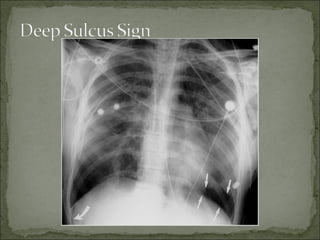

• #18 Chest radiography for evaluation of pneumothorax Although expiratory images are thought to better depict subtle pneumothoraces (the volume of the pneumothorax is constant and hence proportionally higher on expiratory images), a randomized controlled trial revealed no difference in the ability of radiologists to detect pneumothoraces on inspiratory and expiratory images. In patients with underlying pulmonary disease, the classic visceral pleural line may be harder to detect because the lung is hyperlucent, and little difference exists in the radiographic density between the pneumothorax and the emphysematous lung. Ratio of lung size to hemithorax size to estimate pneumothorax size avoids the subjective underestimation of pneumothorax expressed as a percentage of previous lung volume The size of a pneumothorax may be estimated by using the ratio of the lung diameter cubed to the hemithorax diameter cubed. This formula assumes a constant shape of the lung when it collapses and is invalid if pleural adhesions are present. A simple approach to classification of the pneumothorax as small or large involves measuring the distance from the apex of the lung to the top margin of the visceral pleura (thoracic cupola) on the upright chest radiograph. Small pneumothorax: <3 cm distance to the apex Large pneumothorax: >3 cm distance to the apex A supine chest radiograph may depict the deep sulcus sign (very dark and deep costophrenic angle). The anterior costophrenic recess becomes the highest point in the hemithorax, resulting in an unusually sharp definition of the anterior diaphragmatic surface due to gas collection and a depressed costophrenic angle. -------------------------------------------- CT of the thorax When performed on primary spontaneous pneumothorax patients, CT detects multiple blebs and bullae in the setting of negative chest radiographic findings. This may not impact management, as there has been no correlation between number of blebs and recurrence. CT can detect occult pneumothorax in patients who will require mechanical ventilation in trauma and emergency surgery settings. CT has also been shown to be more sensitive than radiography for hemothorax and pulmonary contusion. While the role of CT in trauma patients is evolving, it is controversial whether it significantly alters management and is not indicated in primary spontaneous pneumothorax. CT may have a role in secondary spontaneous pneumothorax, especially to differentiate from giant bullous emphysema. ------------------------------------------------------------------------------------- Ultrasonography Ultrasonography can be used as a possible bedside technique to detect pneumothorax. It may be useful in unstable patients who cannot undergo radiologic studies outside of the emergency department. Many trauma centers are incorporating chest ultrasonography as an adjunct to the Focused Assessment with Sonography in Trauma (FAST) examination used for trauma patient screening. Ultrasonography is operator dependent. -------------------------------

• #21 Pneumothorax in a supine patient. AP supine chest radiograph shows the “deep sulcus” sign of pneumothorax on the right (curved arrow) and a basilar pneumothorax on the left (straight arrows) --------------------------------- Pneumothorax is much more difficult to detect on a supine anteroposterior radiograph. On the anteroposterior view, a deep sulcus sign, representing a deep lateral costophrenic angle, sometimes is a clue to a pneumothorax.